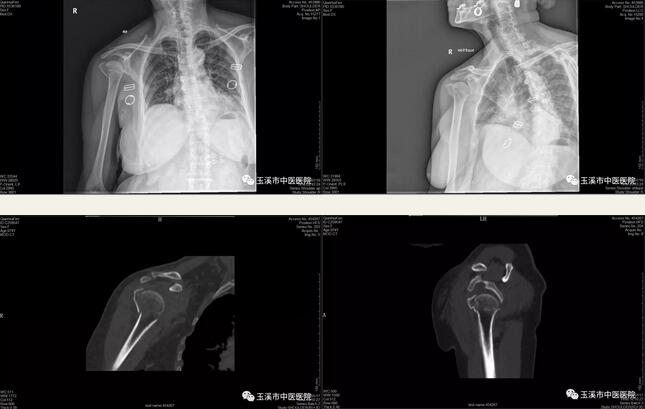

近日,我院骨傷二科(關(guān)節(jié)與運(yùn)動(dòng)醫(yī)學(xué)科)收治了一位74歲老奶奶,因跌倒傷致右肱骨近端粉碎性骨折入院,入院后完善相關(guān)檢查,考慮患者老年存在明顯骨質(zhì)疏松,右肱骨近端4部分骨折,骨折移位明顯,經(jīng)科室討論后予患者行右側(cè)人工全肩關(guān)節(jié)置換術(shù)。

術(shù)前影像學(xué)資料